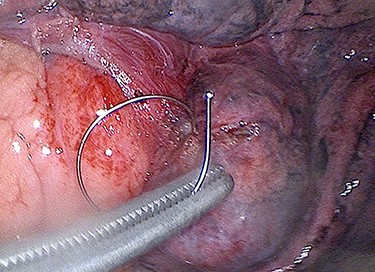

Via a single 4 cm incision for video-assisted thoracoscopic surgery (VATS) (Fig. 2), the embedded endobronchial coil was carefully manipulated out of the superficial lung parenchyma and epicardial fat, and wedge resection of the damaged lung performed. There was no penetrating cardiac injury. The patient made an uneventful recovery.